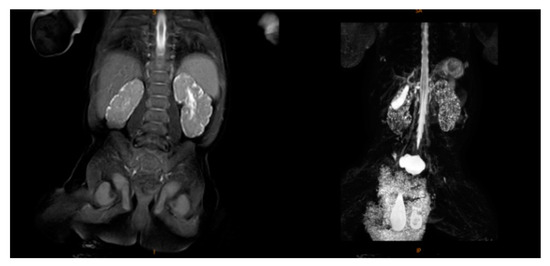

2.2. Supplementary Examination

| Urinary system problems | + | + | + | − | − |